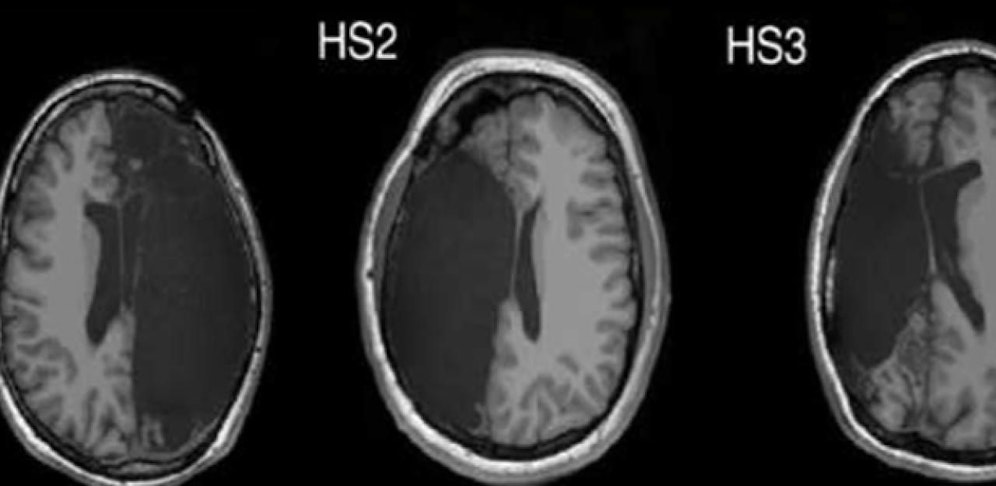

Auf den Bildern der Magnetresonanztomographen sieht man deutlich die dunklen Flecken, wo sich keine Gehirnmasse befindet.